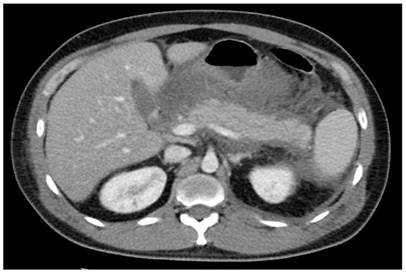

Ante el cuadro sospechoso de patología con afección pancreática (pancreatitis con posible sobreinfección), se decidió realizar estudios de extensión. Los paraclínicos de ingreso mostraban amilasa pancreática en 1229 mg/dL, leucocitosis (21 000/mm3), neutrofilia (92 %) e hipertrigliceridemia (3980 mg/dL), lipoproteína de muy baja densidad (VLDL) elevado (80 mg/dL) con colesterol total (120 mg/dL), lipoproteína de alta densidad (HDL), electrolitos, función renal, función hepática y procalcitonina dentro de los parámetros normales (de esta forma se descartó la probabilidad de un proceso infeccioso); adicionalmente, se solicitó una tomografía axial computarizada (TAC) de abdomen, la cual reportó derrame pleural bilateral, signos de pancreatitis edematosa intersticial asociada con múltiples colecciones peripancreáticas agudas y líquido libre abdominal, considerando el diagnóstico de pancreatitis Balthazar C-D (Figura 1), con puntaje de gravedad clínica APACHE de 8 puntos y Marshall de 2 puntos.